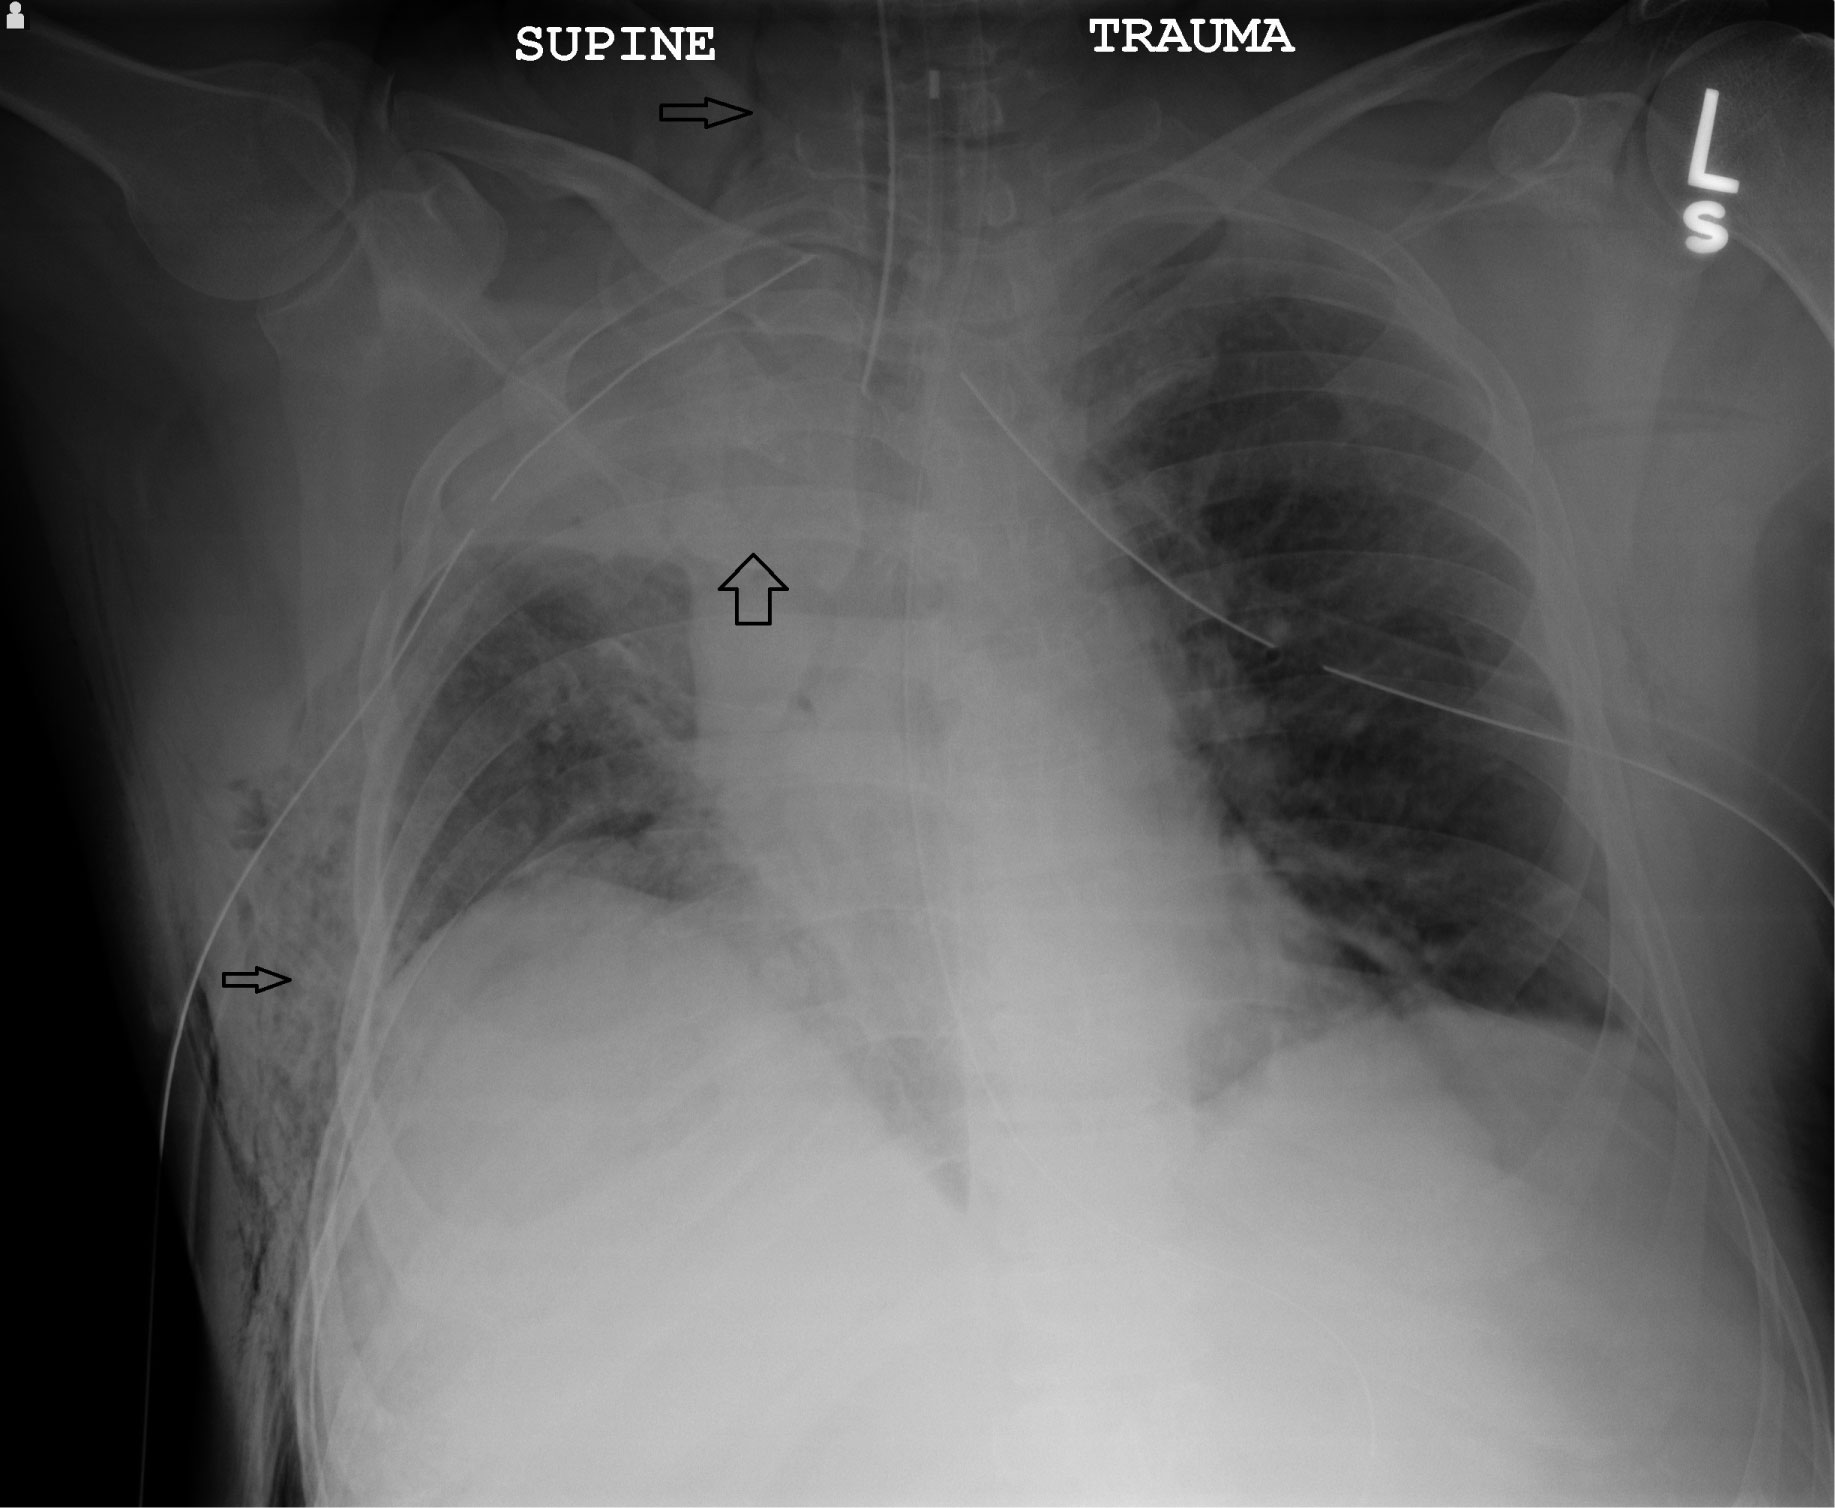

A 50-year-old man was ejected during an ATV collision. On arrival to the trauma center, he was endotracheally intubated for hypoxemic respiratory distress and was noted to have palpable subcutaneous air and decreased breath sounds; thoracostomy tubes were placed bilaterally. New-onset atrial fibrillation with rapid ventricular response (heart rate > 160) was found with ST-segment elevation most pronounced in Inferior leads (Figure 1) Chest radiograph confirmed severe right-sided pulmonary contusions (Figure 2) and CT showed multiple right and left-sided rib fractures and sternal fracture. He also sustained a subdural hematoma, subarachnoid hemorrhage, grade 1 hepatic injury, and left elbow fracture-dislocation. Repeat EKG after esmolol infusion showed return to sinus rhythm and confirmed ongoing ST-segment elevation. Bedside echocardiogram showed apical akinesis but no valvular abnormalities and left ventricular ejection fraction of 60%. Emergent coronary catheterization revealed occlusions of distal LAD and RCA vessels; all other vessels were without disease. After a 3-week hospitalization requiring tracheostomy for prolonged mechanical ventilation he eventually had an excellent recovery.

Figure 2: Anterior-posterior chest radiograph after bilateral thoracostomy tubes showing right upper lobe density (wide arrow) and right-sided subcutaneous air in chest wall and neck (narrow arrow). View Figure 2